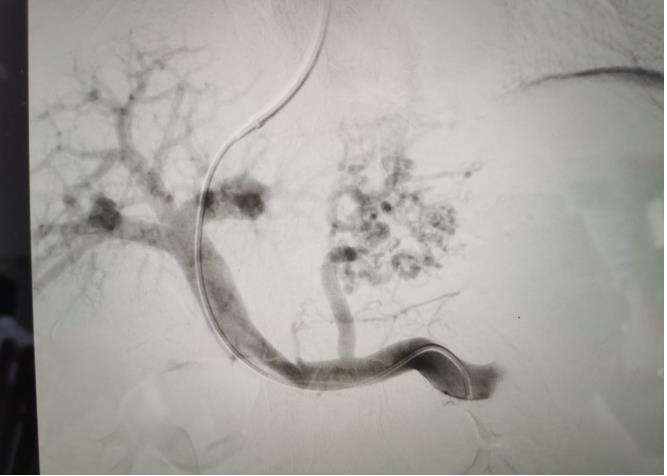

經(jīng)過我院血管介入科醫(yī)療團(tuán)隊(duì)的精心準(zhǔn)備,患者在數(shù)字減影血管造影機(jī)(DSA)導(dǎo)引下�,順利經(jīng)頸靜脈入路進(jìn)入下腔靜脈并成功穿刺了門靜脈右支主干,術(shù)中栓塞了曲張的胃冠狀靜脈-食管靜脈叢將支架植入肝實(shí)質(zhì)內(nèi)�����,支架兩端分別置于門靜脈和肝靜脈內(nèi)�,術(shù)程歷時(shí)2小時(shí),術(shù)中患者時(shí)刻保持清醒���,手術(shù)切口僅5毫米����,術(shù)后第2天恢復(fù)飲食,腹脹�、腹水癥狀明顯好轉(zhuǎn),未出現(xiàn)嘔血�、黑便及肝性腦病等并發(fā)癥,術(shù)后第3天康復(fù)出院�。